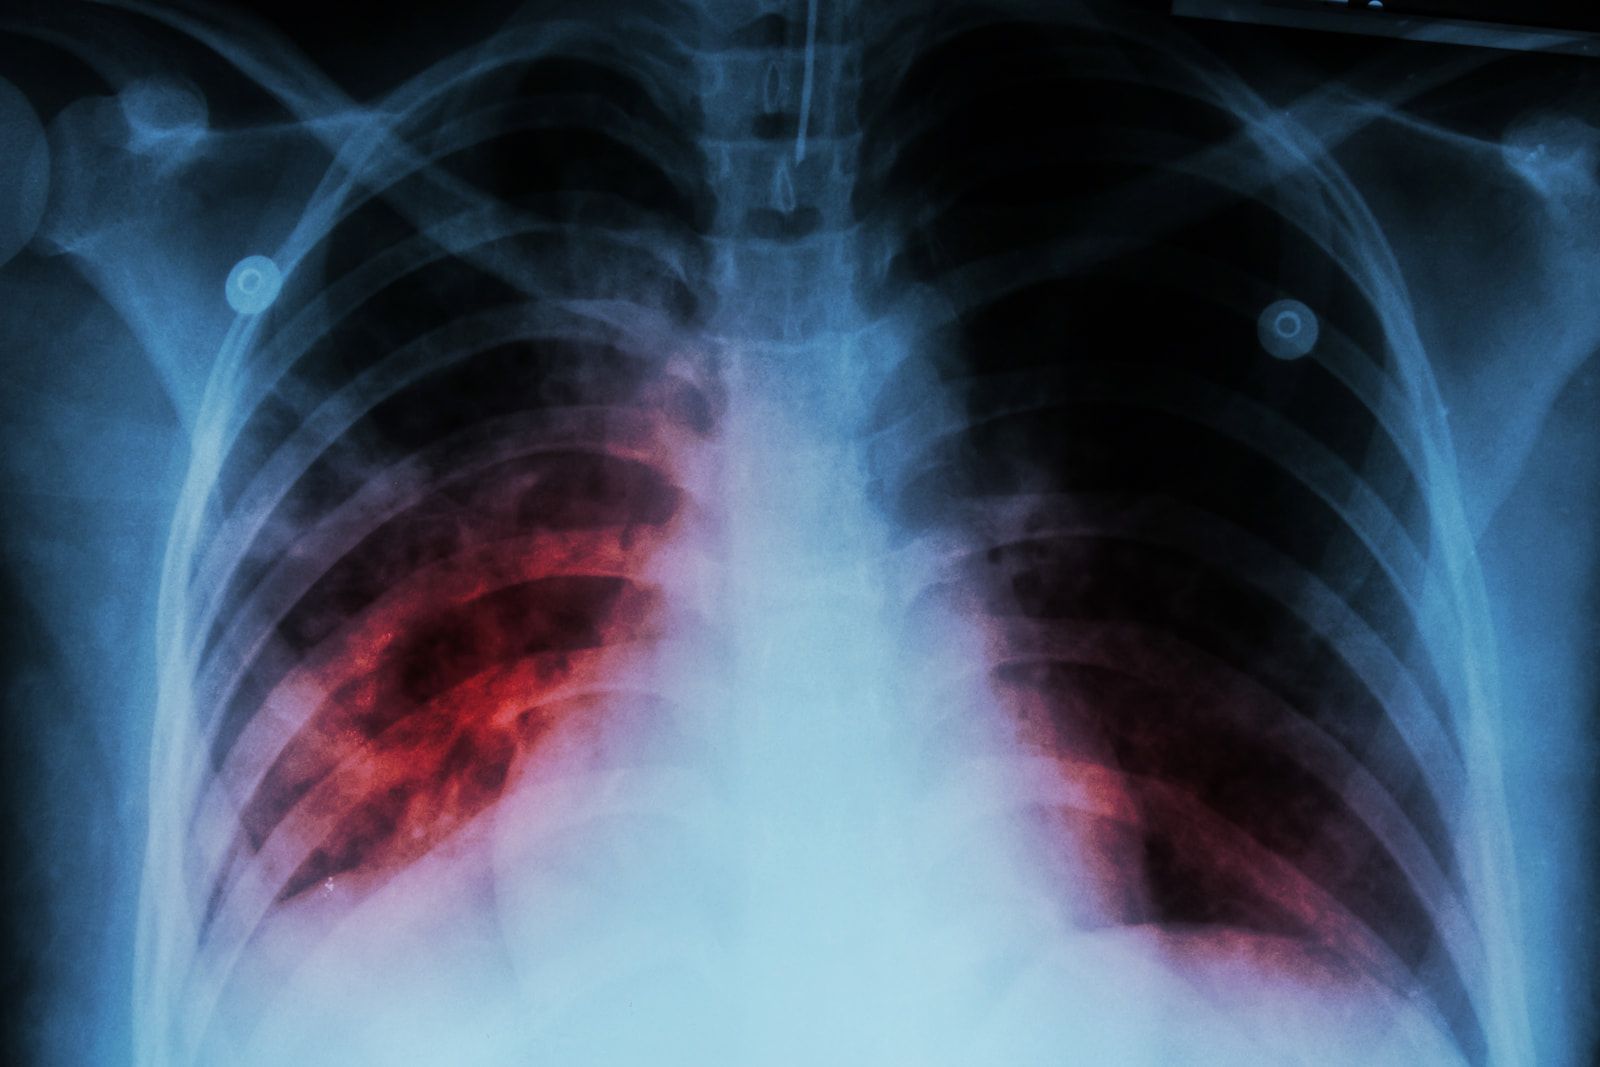

Tuberkulos dödar över 1,6 miljoner per Är. Men det finns hopp vid horisonten, med det nya M72-vaccinet. Det första nya tuberkulosvaccinet pÄ ett Ärhundrade.

Kampen mot tuberkulos  har prÀglats av en pÄtaglig frÄnvaro: ett modernt, effektivt vaccin. Samtidigt som tuberkulos fortsÀtter att ha en stÄr pÄverkan, med 1,6 miljoner dödsfall 2021 och över 10,6 miljoner drabbade individer, har man tvingat förlitat sig pÄ det hundra Är gamla Bacille Calmette-Guérin (BCG) -vaccinet. Dess begrÀnsade skydd, sÀrskilt mot pulmonell tuberkulos hos vuxna och ungdomar, visar hur brÄttom det Àr med ett alternativ.